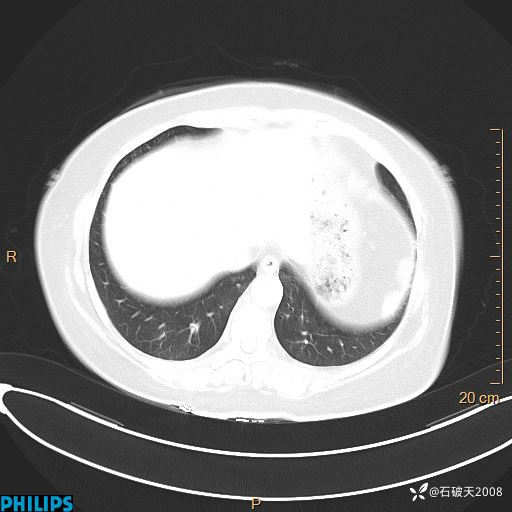

肺结节病?纵膈型肺癌?淋巴瘤?有点意思,欢迎围观

女 52岁 主 诉:咳嗽10余天,咳痰2天。

现病史:10余天前无明显诱因出现咳嗽,呈阵发性干咳,伴咽喉部发痒,无咽痛,无咳痰,无鼻塞、流涕、打喷嚏,无发热、畏寒、寒颤,无头痛、头晕,无胸闷、胸痛,无反酸、烧心,无腹痛、腹泻,无尿频、尿急,无皮疹等,在当地诊所求治,给予口服药物治疗(具体不详),病情无好转。遂在当地社区卫生服务中心开具口服药物治疗(具体不详),疗效欠佳。2天前出现咳痰,在我院门诊求治,行胸部CT提示肺部感染,建议住院,患者要求口服药物治疗,目前仍咳嗽、咳白色粘痰,白天量多,夜间自觉喉部喘鸣音,遂再次来院就诊,以“肺部感染”为诊断收入院。发病以来,神志清,精神可,饮食可,夜间睡眠差,大小便正常,近期体重无明显变化。

动脉期